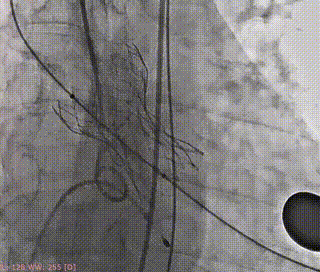

瓣叶交界贴合释放瓣膜

23mm球囊后扩

最终造影评估